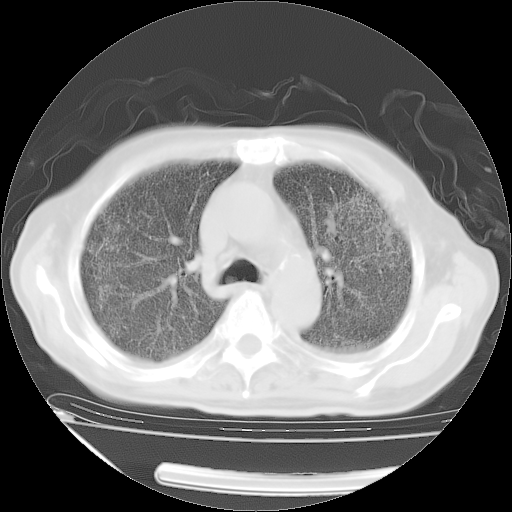

甲强龙80mg/日+抗结核治疗(异烟肼+利福霉素+乙胺丁醇)10天。复查肺部CT。

治疗10天肺部CT